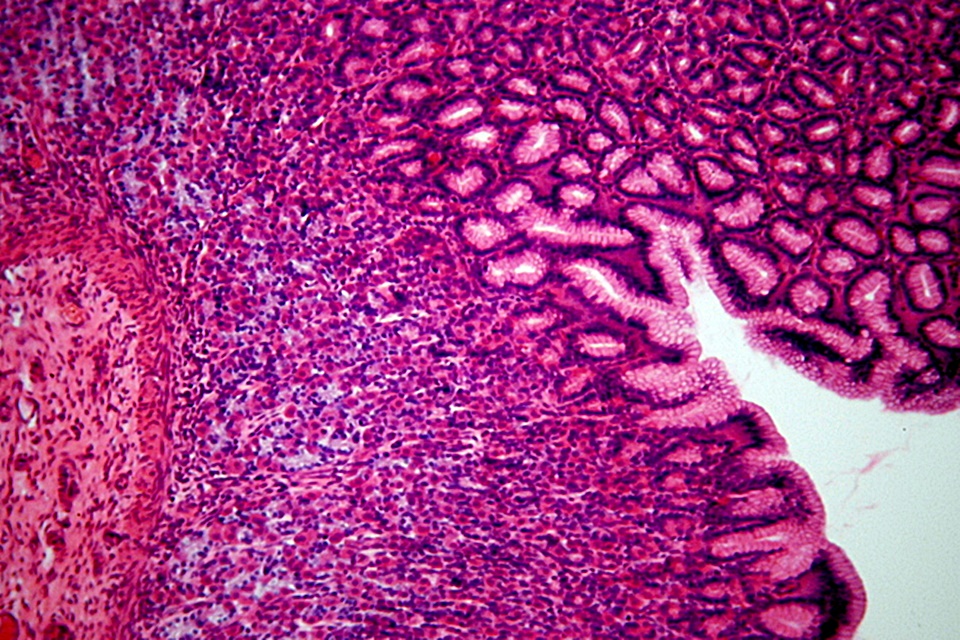

– Objawy wścieklizny obejmują różne dysfunkcje neurologiczne. Przebieg choroby zależy od gatunku i charakteru zakażonego zwierzęcia. Najbardziej wiarygodnymi wskaźnikami są nagłe zmiany zachowania, na przykład nagły paraliż, który postępuje z czasem, jest jednym z klasycznych objawów. Zmiany w zachowaniu mogą obejmować nagłą utratę apetytu, lękliwość lub nerwowość, drażliwość i nadpobudliwość. Spokojne dotąd psy, mogą stać się jeszcze bardziej spokojne, podczas gdy inne psy mogą być bardziej pobudliwe. W pierwszym okresie choroby, zachowanie psa może stać się dziwne. Pies może nie rozpoznawać swojego właściciela lub intensywnie lizać różne dziwne rzeczy. Może nieprzerwanie lizać, gryźć i drapać miejsce, w którym został ugryziony. W miarę postępu choroby zmysły psa mogą stać się nadwrażliwe. Może dojść do paraliżu gardła i mięśni pyska, co prowadzi do dobrze znanego objawu, jakim jest pojawienie się piany w jamie ustnej. Może pojawić się dezorientacja, brak koordynacji ruchowej i oszołomienie, spowodowane paraliżem tylnych kończyn – mówi dr n. wet. Michał Ceregrzyn, ekspert Kocham – Dbam o zdrowie – Chronię.

Istnieją dwie postacie wścieklizny:

- porażenna,

- szałowa.

Postać szałowa charakteryzuje się skrajnymi zmianami zachowania, w tym nadmierną agresją i próbami ataku.

Objawami postaci porażennej są kolejno:

- osłabienie,

- utrata koordynacji,

- paraliż.